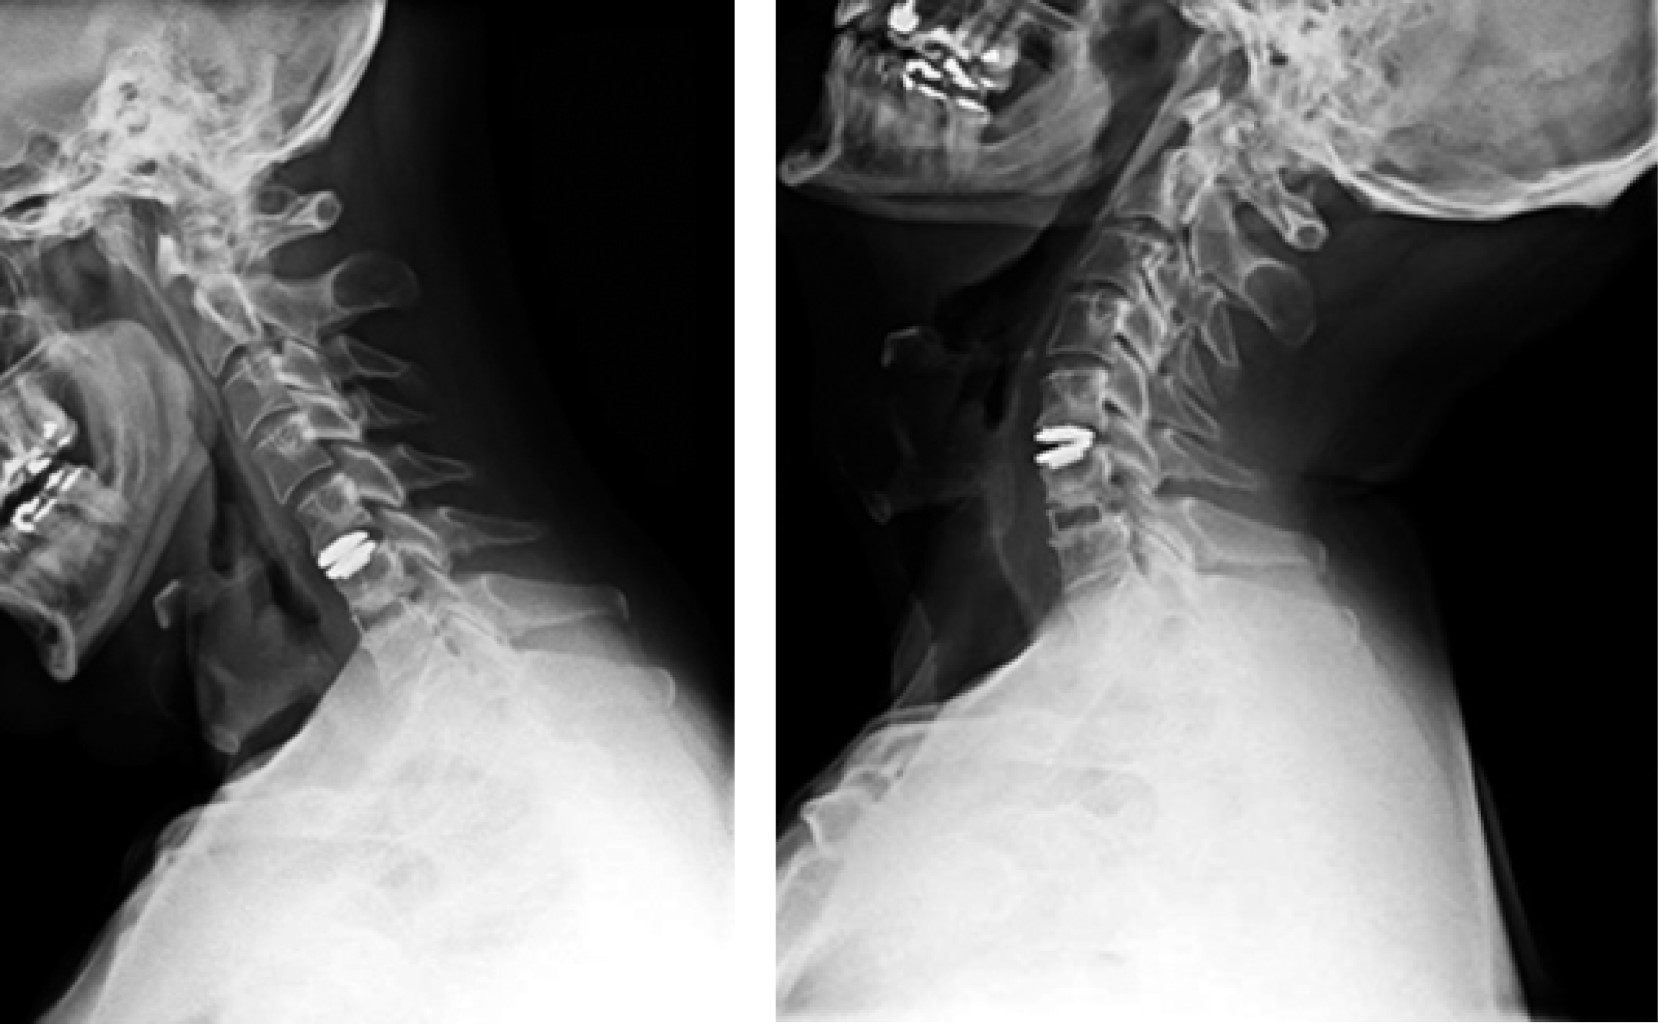

Figure 3